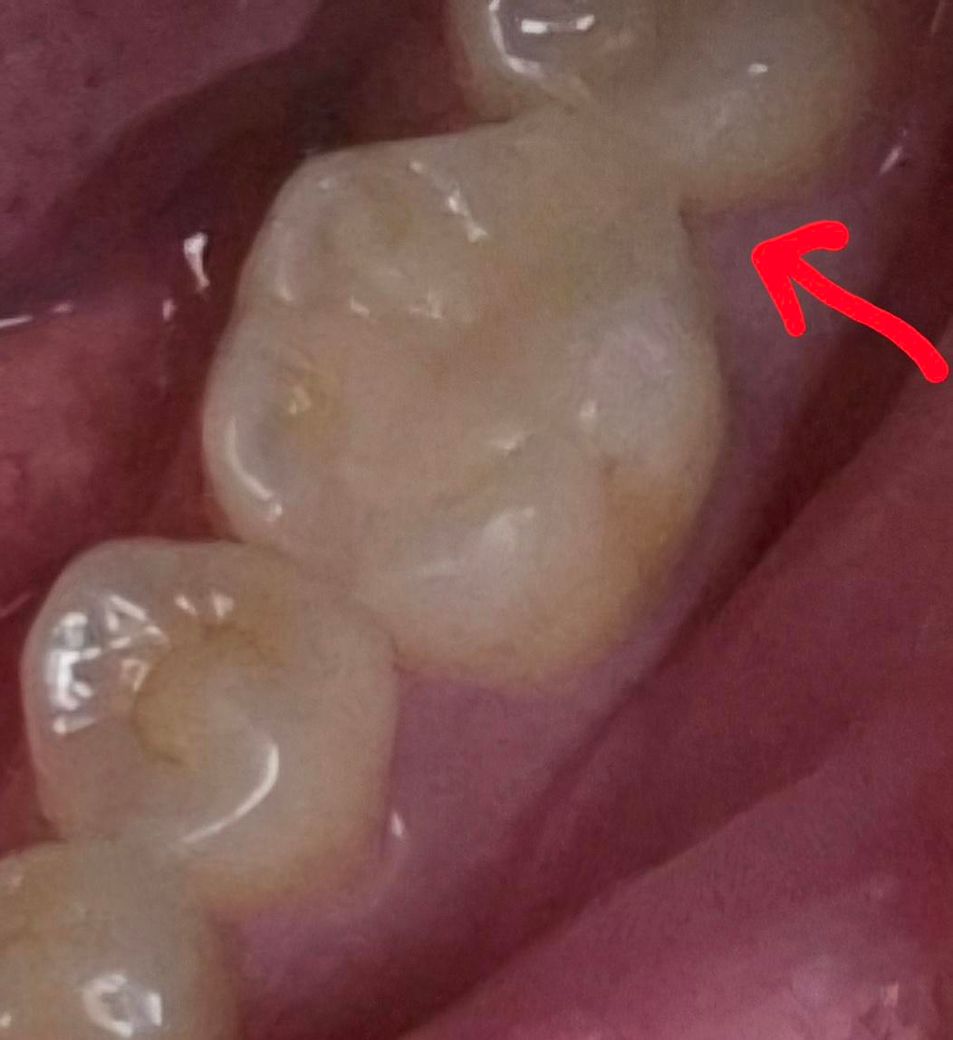

깊은 충치에다가 인접면도 썩어서 밑에 살짝 gi깔고 레진으로 덮었습니다 근데 인접면쪽 레진 원래 이렇나요? 치실은 들어가는데 모양이 좀.... 이것도 처음엔 인접면쪽이 사각형 모서리처럼 너무 각져서 음식물이 너무 잘끼고 치실도 나올때 계속 걸리니까 혀 있는 안쪽 인접면쪽(화살표 반대쪽) 조금 갈아달라고 2번이나 수정한거에요 그래도 각져있구... 진짜 너무 스트레스인데 도와주세요 정상인건지 모양잡는걸 못하시는건지 알고싶어요 못하시는거면 더 요구안하고 다른치과가서 다듬어달라하면 해줄려나요..ㅠㅠㅠ...

치료 전 사진을 봐야 정확하겠지만 지금 수복물의 모양으로 봐서는 원래 치아도 그 옆 어금니와 정상적인 접촉면을 형성하고 있진 않았을 것 같습니다. 즉, 형태이상의 일종인데 거기서 어쩔 수 없이 충치 제거 후 레진으로 수복했으니 저렇게 모양이 나오는 겁니다. 조금 더 둥글게, 부드럽게 다듬을 순 있을 것 같습니다.